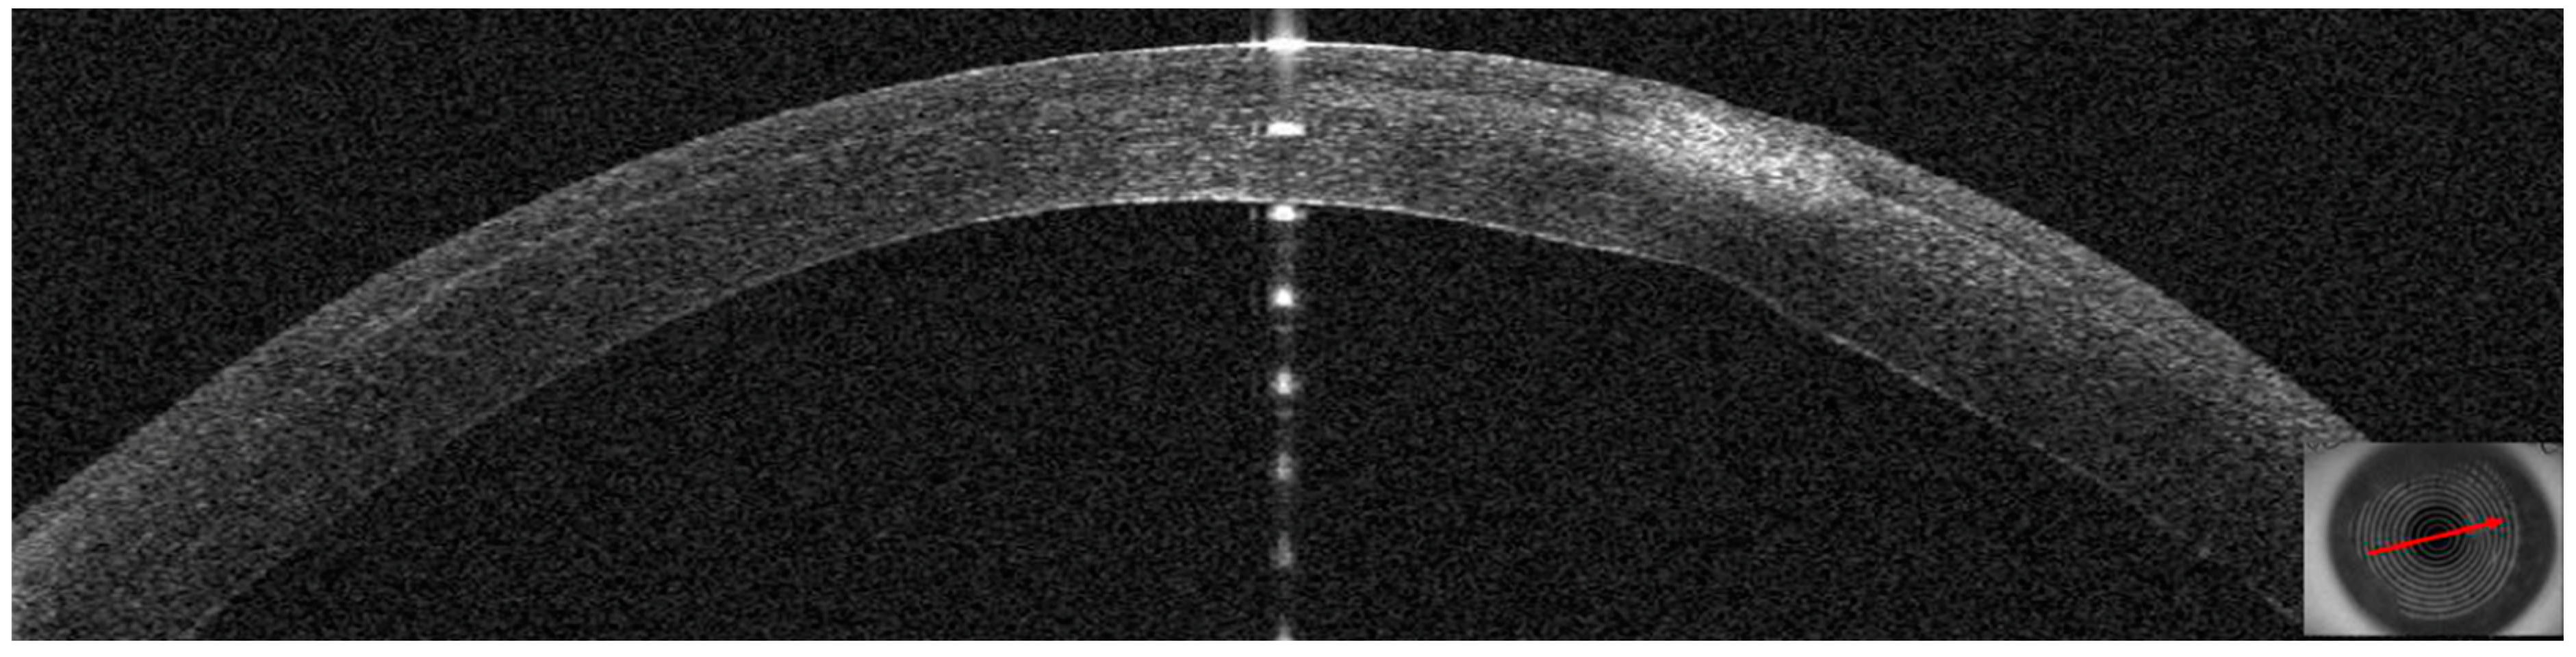

3.3. Patient #3